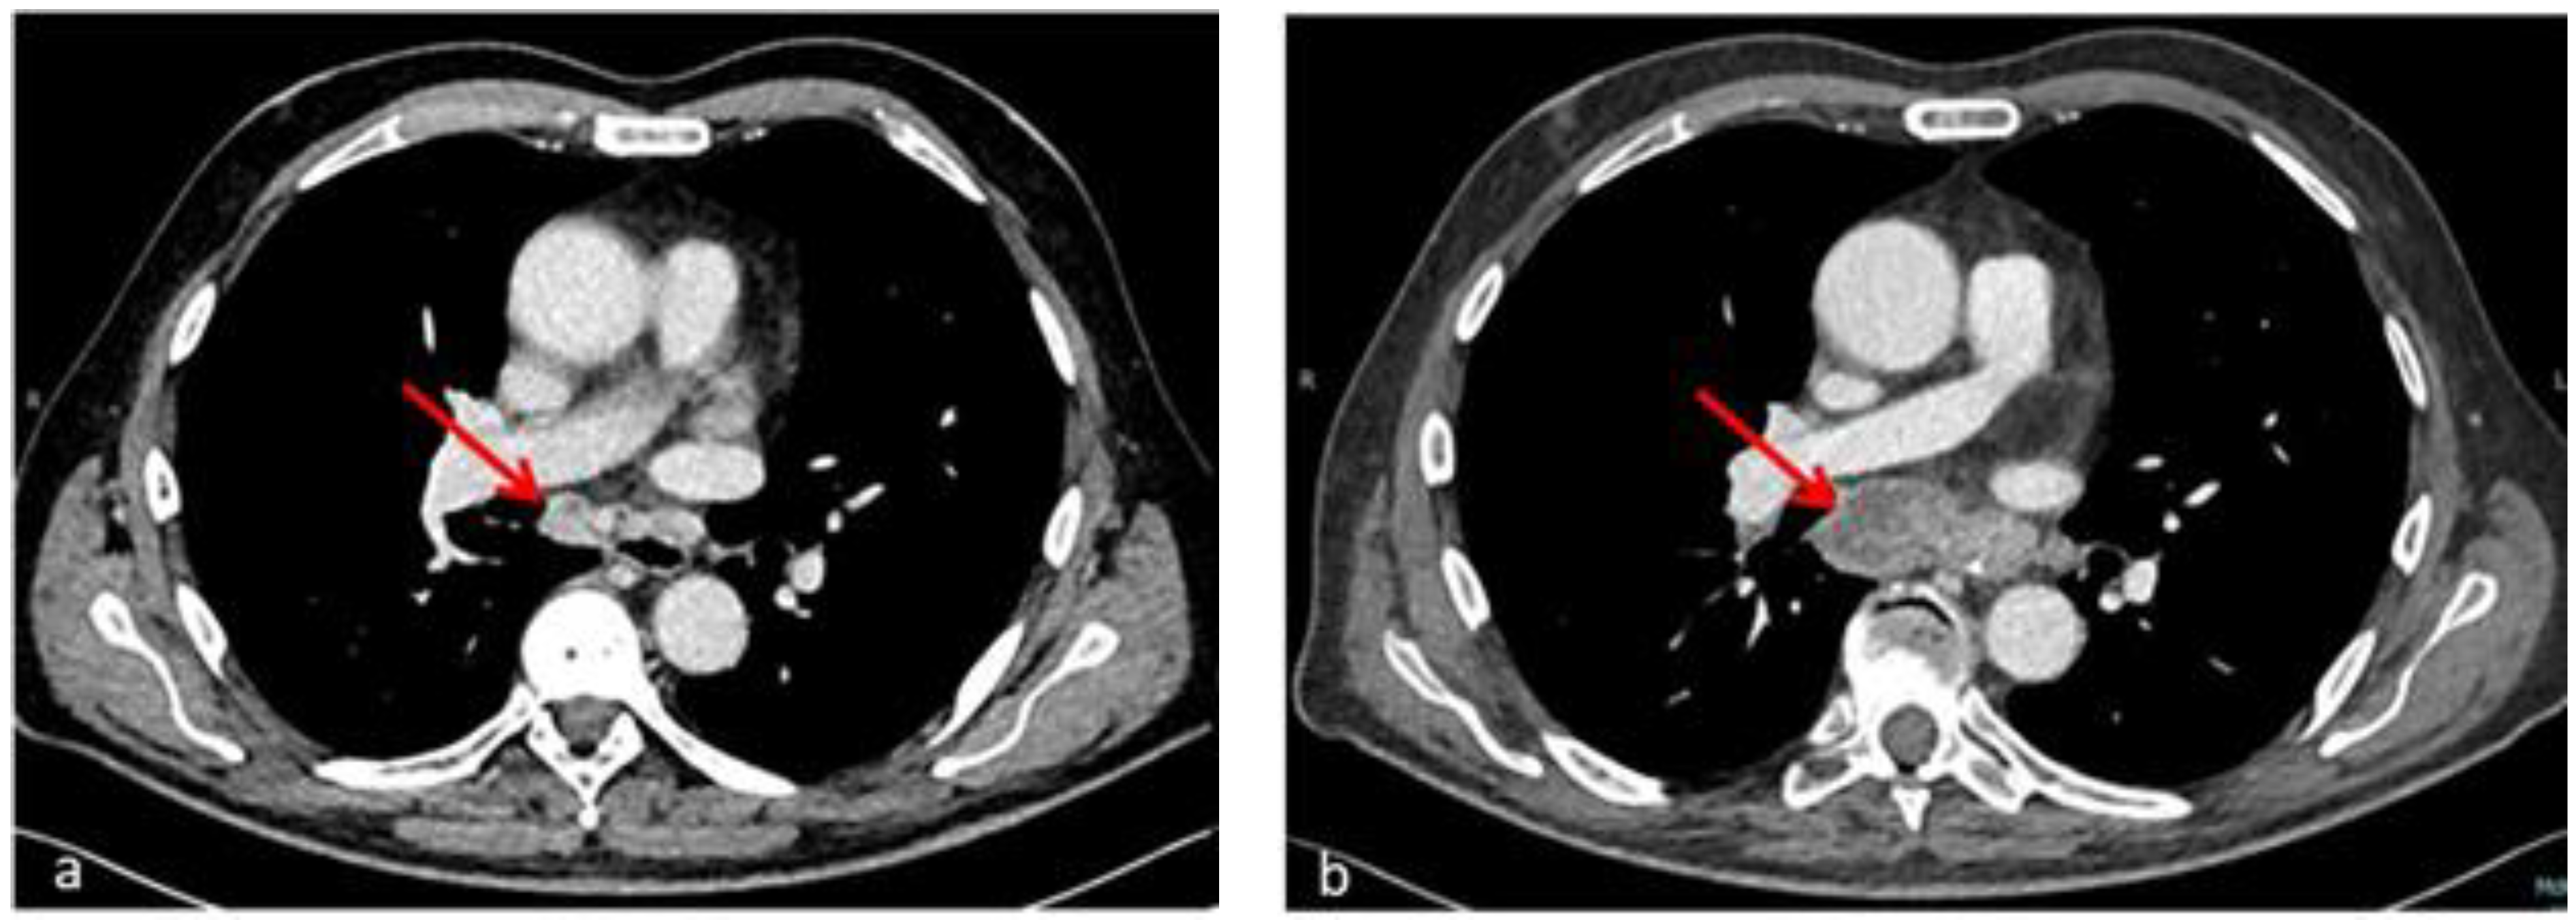

2. Case Description